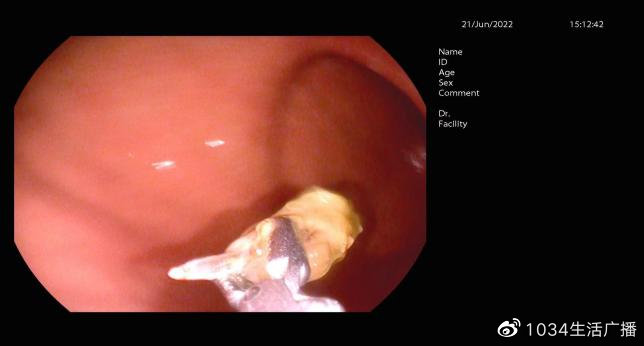

沈阳市第四人民医院消化内镜中心为徐女士进行了胃镜检查:发现枣核尖端已经将胃窦黏膜刺破出现溃疡,如果再晚来几天,枣核极有可能把胃壁刺穿、造成穿孔。医生应用异物钳将异物取出体外。